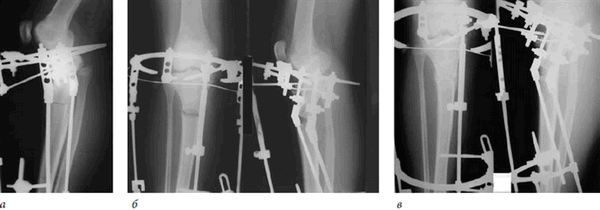

В связи с наличием функционального и косметического дефекта было принято решение об оперативной коррекции (рис. 5, 6). Ребенку была выполнена остеотомия большеберцовой кости в в/3, осуществлено наложение комбинированного аппарата внешней фиксации с дальнейшей коррекцией оси и укорочения по Г.А. Илизарову (рис. 7).

Рис. 7. Этапы коррекции в аппарате внешней фиксации

Деформация была устранена, аппарат демонтирован после созревания регенерата (рис. 8).